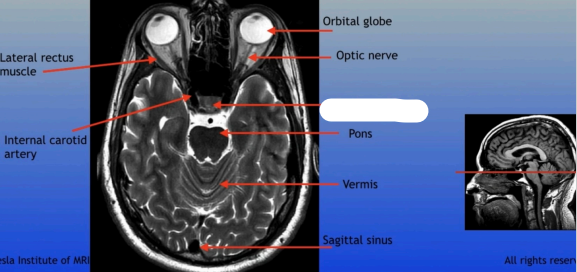

Lateral Rectus Muscle

Internal Carotid Artery

Orbital Globe

Optic Nerve

Pons

Vermis

Sagittal Sinus